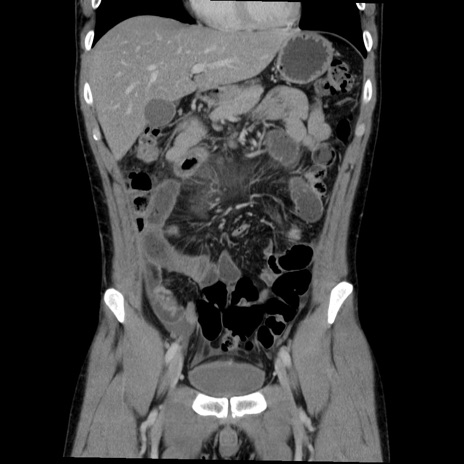

症例36(冠状断像)

【症例】20歳代 男性

【主訴】心窩部痛

【現病歴】今朝より上腹部痛あり。一旦軽快していたが再度出現したため救急要請。昨日夕に白身の魚を含む刺身を食べた。

【身体所見】BP 136/89mmHg、HR 74/min、BT 37.0℃、腹部:膨満、軟、心窩部に圧痛あり。反跳痛なし、筋性防御なし、腸雑音やや亢進あり。

【データ】WBC 17700、CRP 0.48